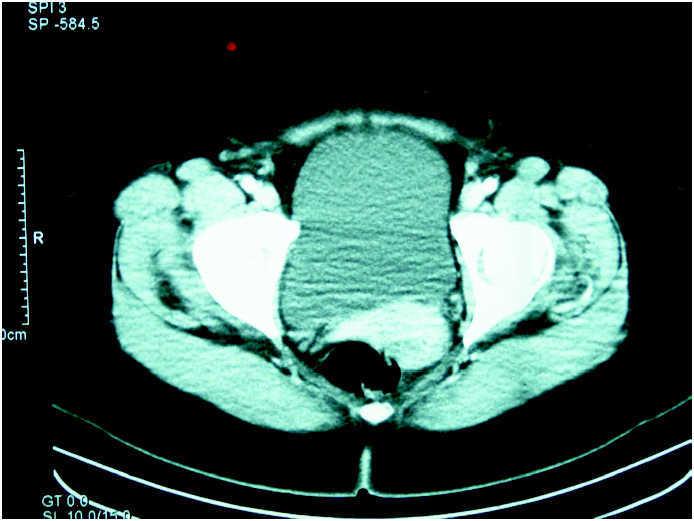

En el estudio de imagen se observa una imagen quística, tabicada, de 16 cm de diámetro, que parece depender del anejo derecho (fig. 1). En la analítica realizada se detecta un leve incremento del antígeno CA 125, con un antígeno CA 19.9 dentro de los límites establecidos.

Figura 1. Tomografía computarizada de abdomen inferior y pélvico en la que se observa una imagen quística de 16 cm, que parece depender de anejo derecho.